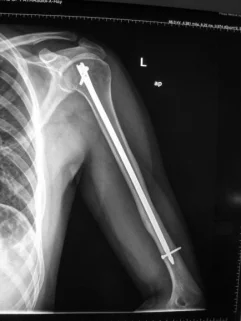

Humeral Shaft Fracture- Management

- Conservative: U-shape slab) / splint / orthosis

- Gravity maintains reduction

Humeral Shaft Fracture

- Management:

- Operative: (plate or IMN)

- Indications:

- Sever displaced Unreduced,

- Bilateral,

- multiple injuries

- floating elbow,

- Needs to use crutches

- Patients’ preference (active, athlete)